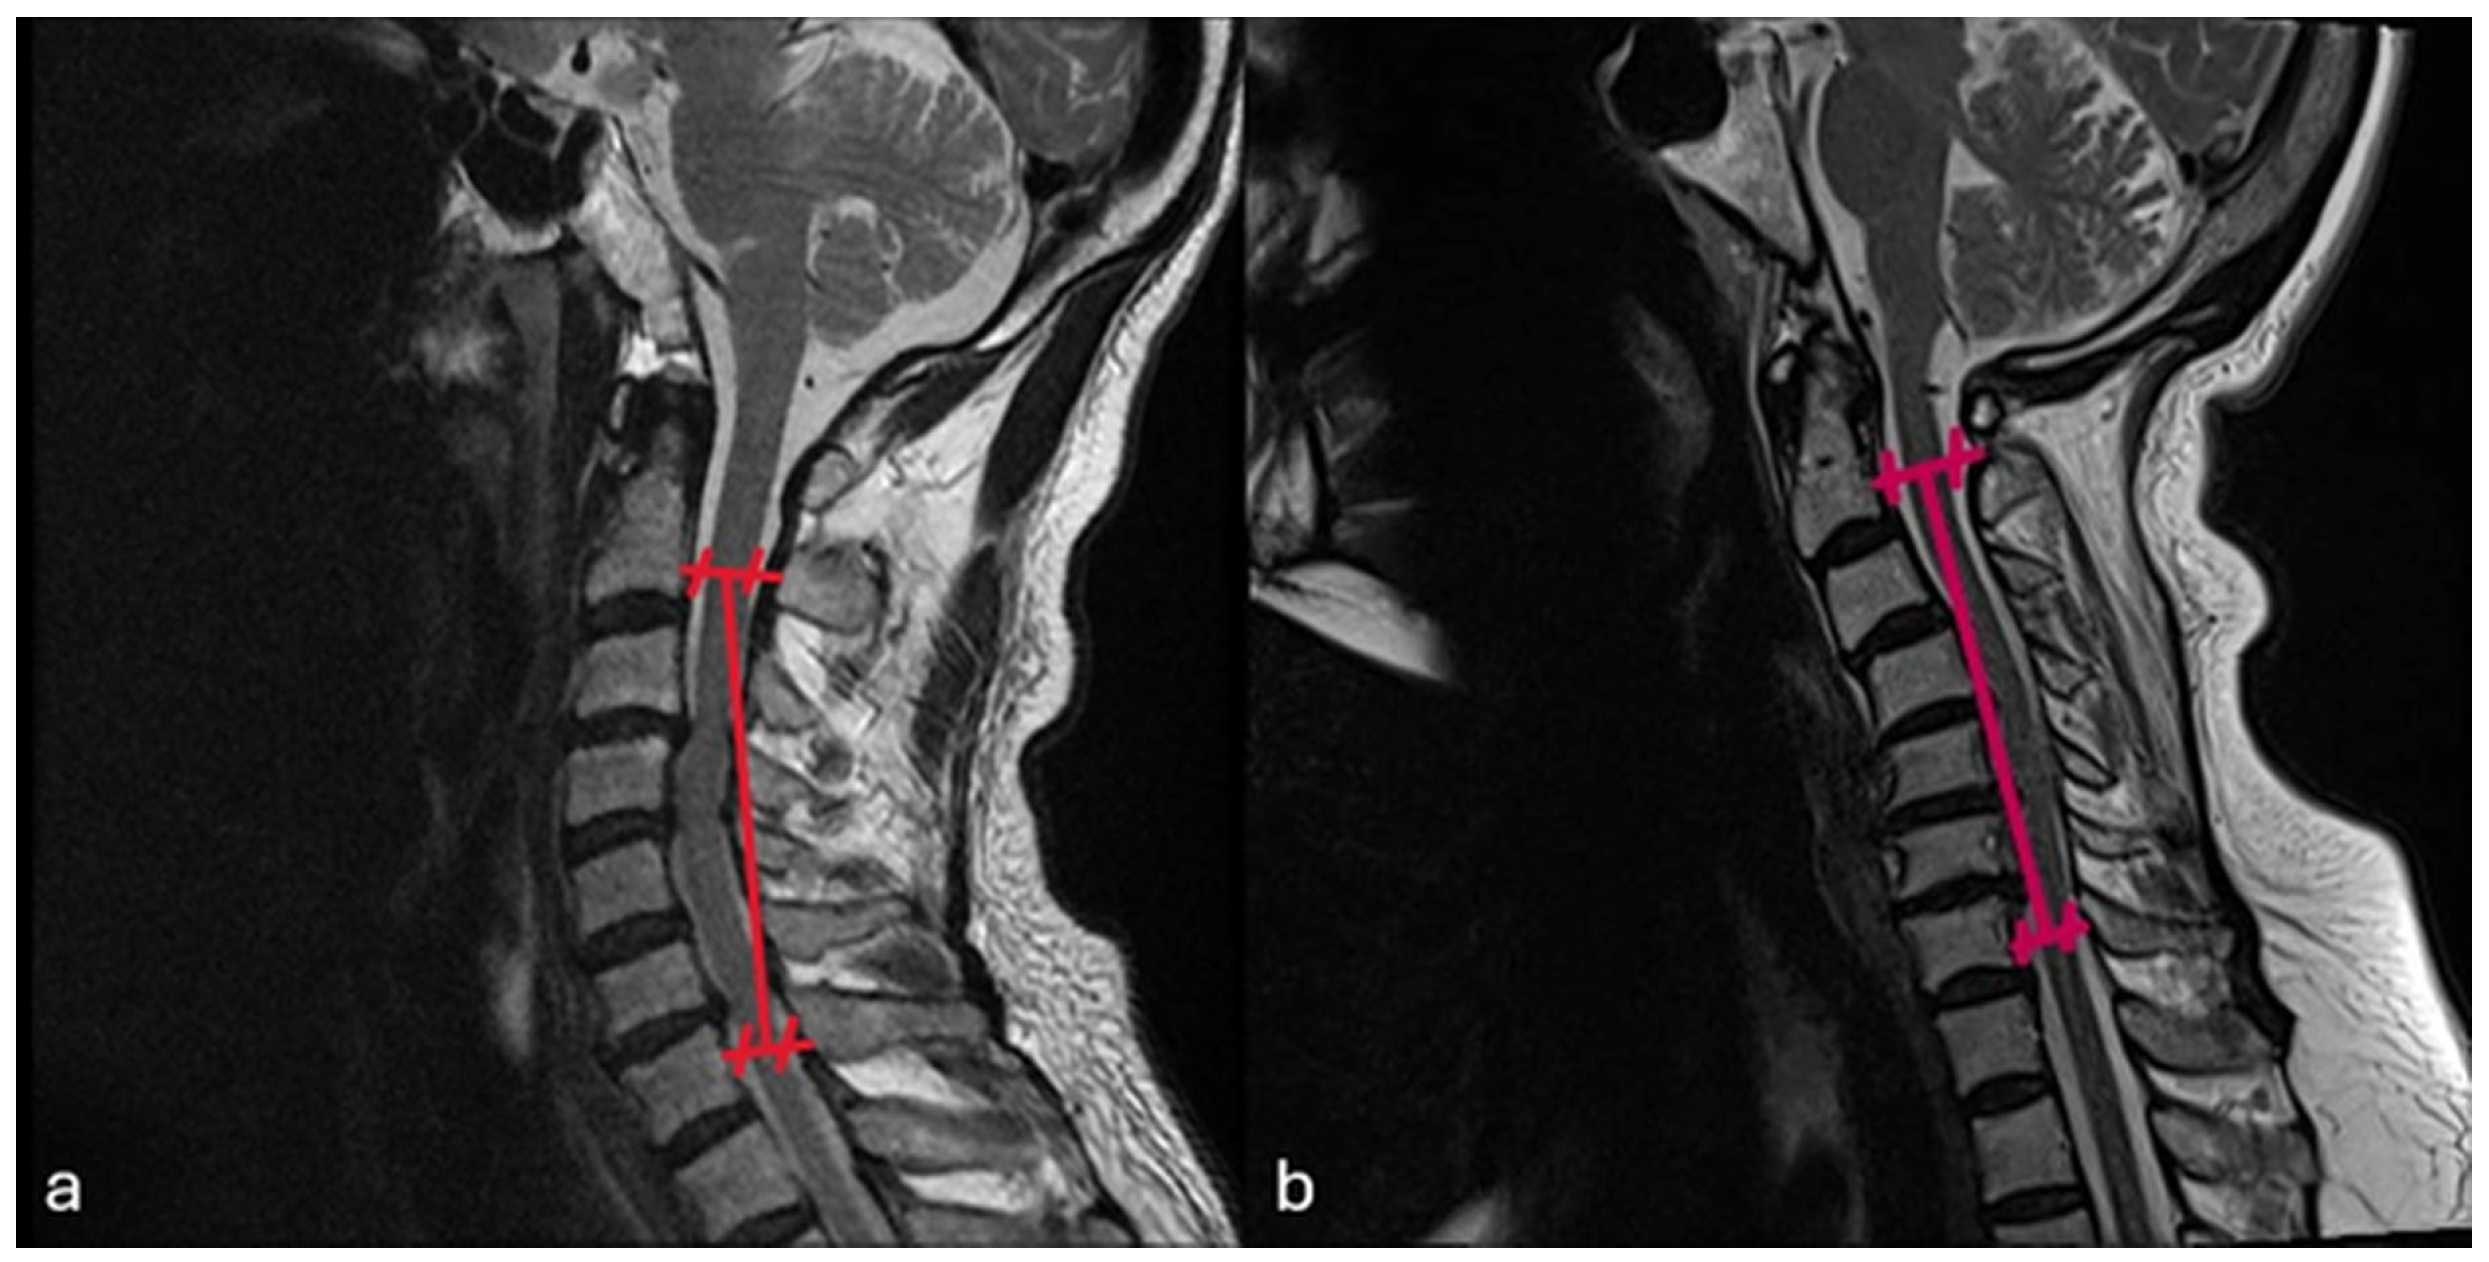

2.3. Dependent Variables (Radiological)

- Postoperative last control C2–C7 Cobb angle

- Postoperative last control cervical alignment

- Postoperative last control K-line

Preoperative C2–C7 Cobb Angle vs. Postoperative Last Control C2–C7 Cobb Angle

Preoperative Cervical Alignment Category vs. Postoperative Cervical Alignment Category

Preoperative K-Line vs. Postoperative K-Line